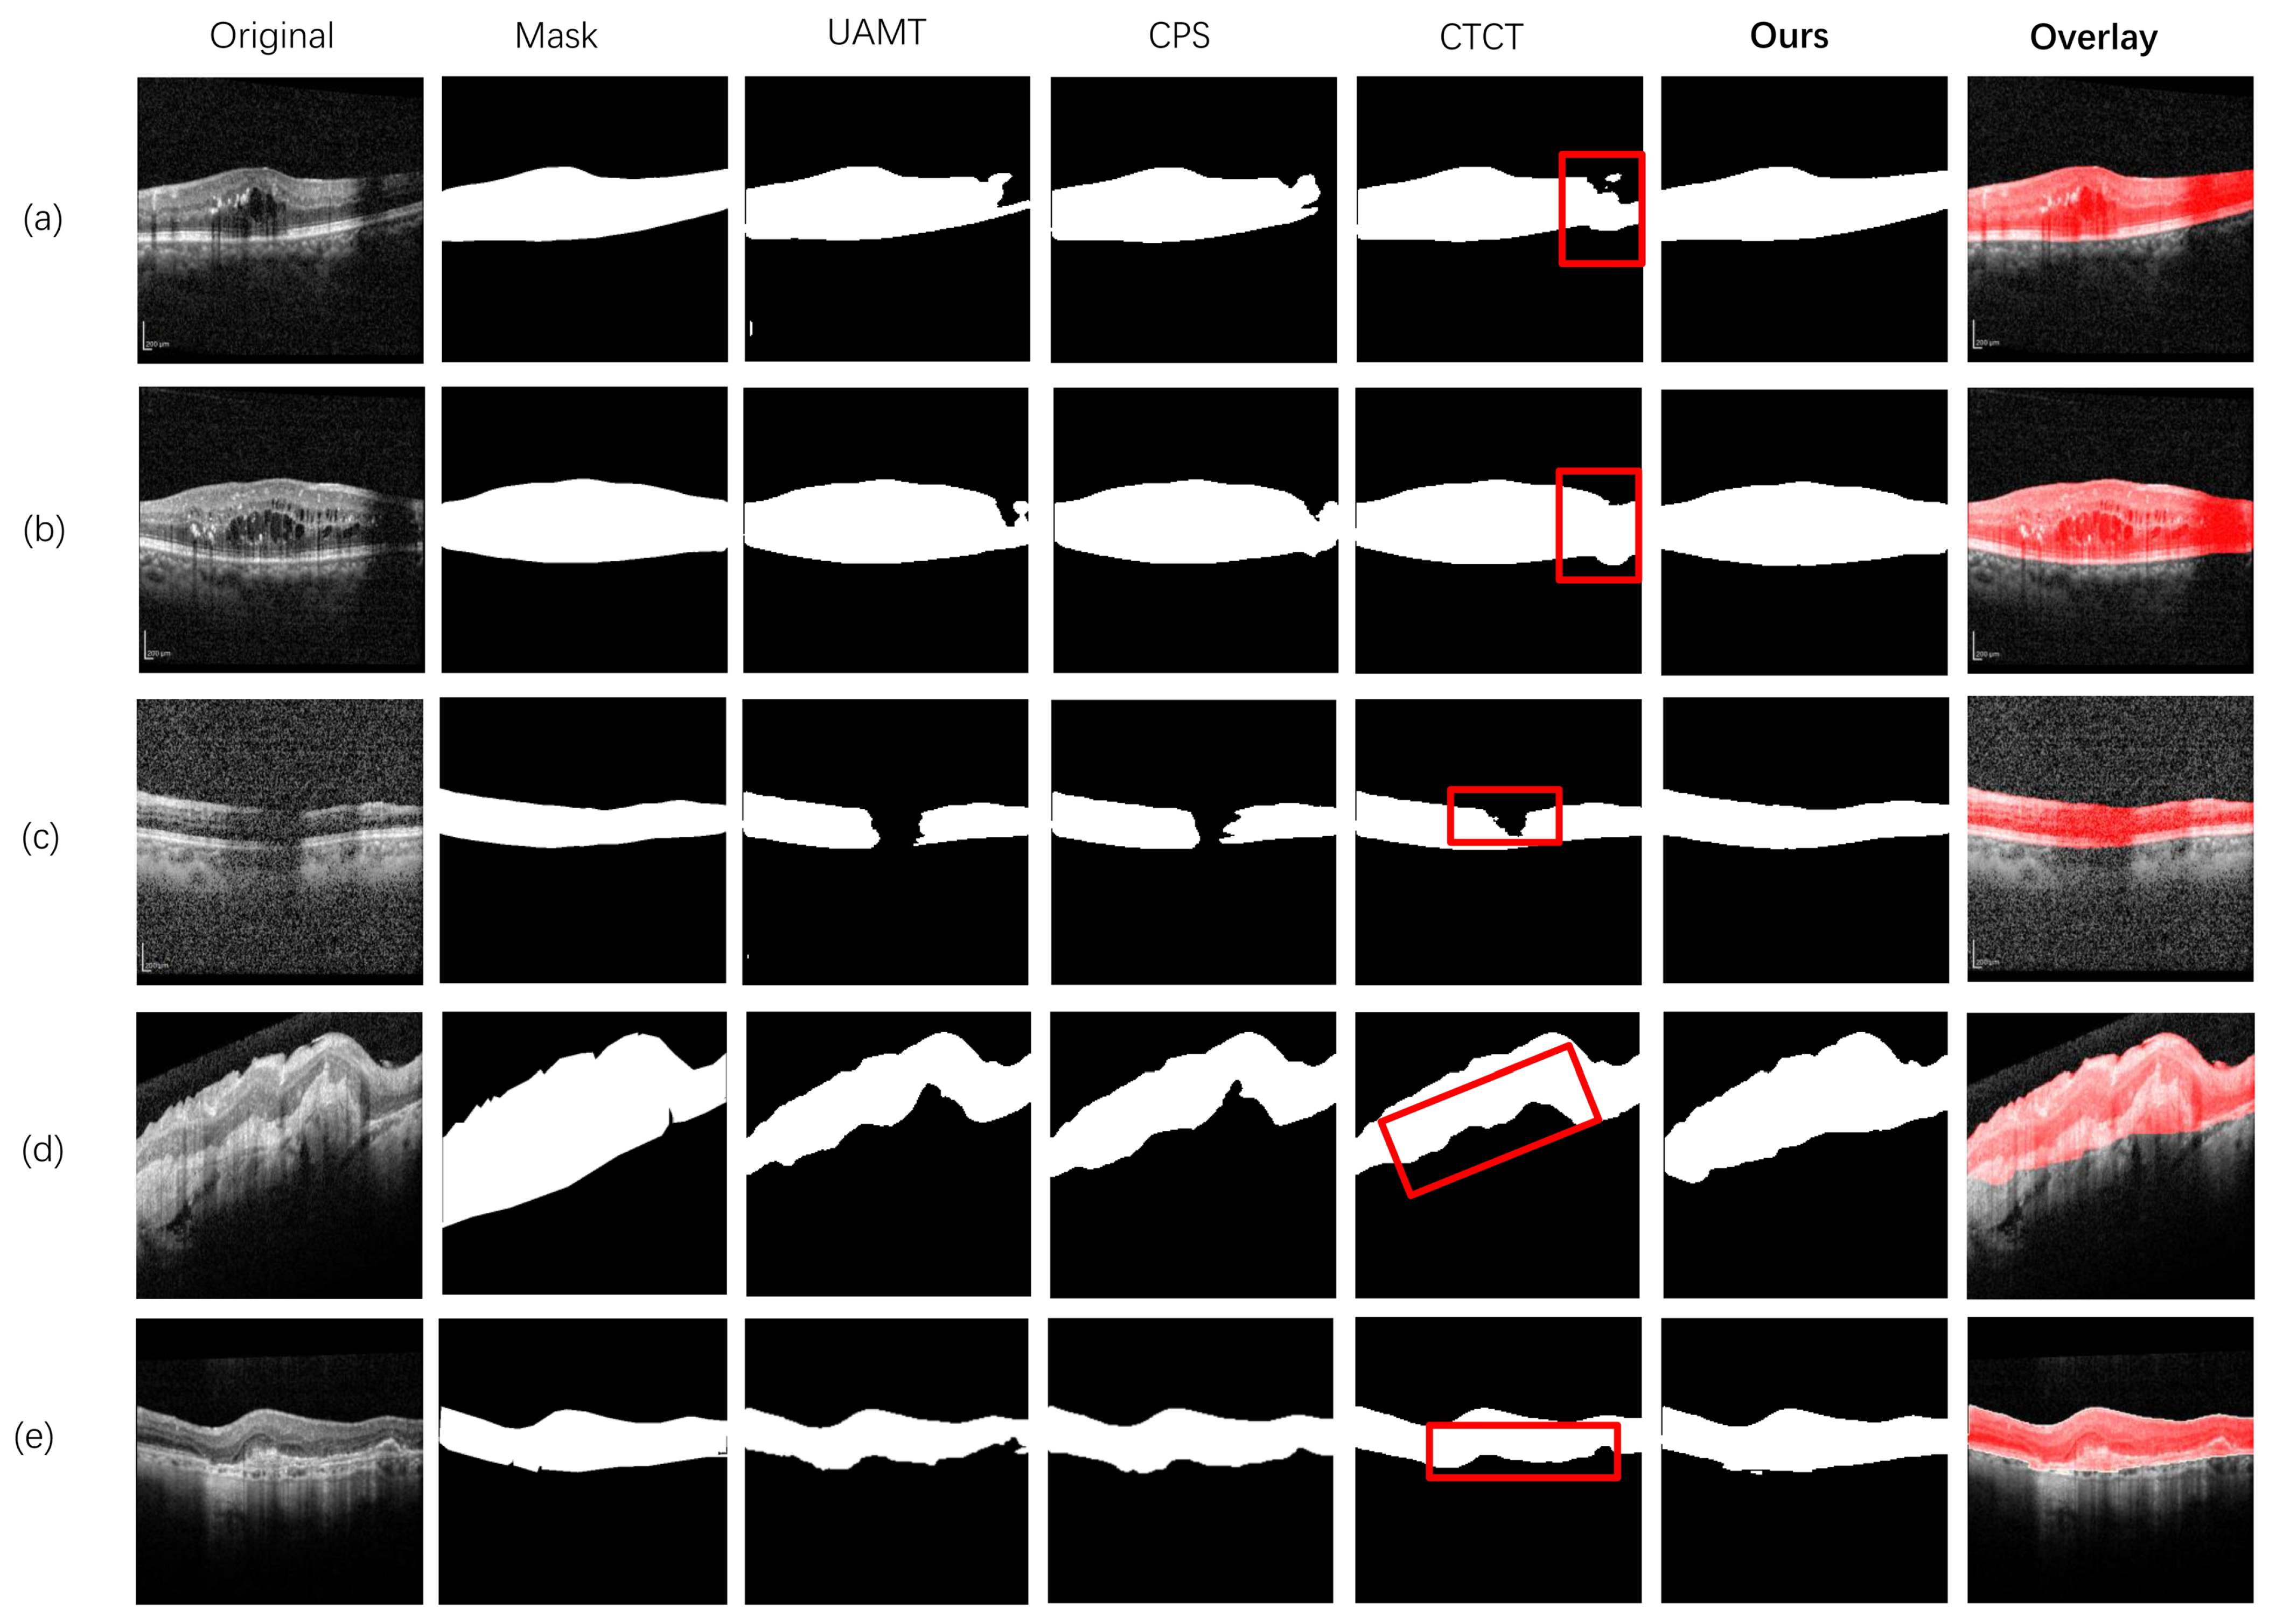

In Figure 9, a few challenging OCT images show blurred or broken retinal borders, such as Figure 9a–c. According to the segmentation results, our proposed method achieved precise segmentation results for this type of image. Specifically, the retina boundary was broken on the right side of Figure 9a,b and in the middle area of Figure 9c. Our algorithm successfully segmented these regions, whereas the baseline network could not. As shown in Figure 9d,e, due to edema and changes in retinal morphology, it was hard to distinguish the tissue boundary from the surrounding area, making segmentation difficult. In this case, our algorithm delivered very close segmentation results. Although there was severe deformation of the retina in Figure 9d, most of the regions were still segmented.

Figure 9. Comparison of the segmentation results. There are seven columns, including the original image, the labeled image, the UAMT segmentation result, the CPS segmentation result, the CTCT segmentation result, and the visualization of the segmentation result of our algorithm and the overlay on the original image. In the red boxes, the baseline model predicts incorrect results, while our algorithm produces satisfactory segmentation results.